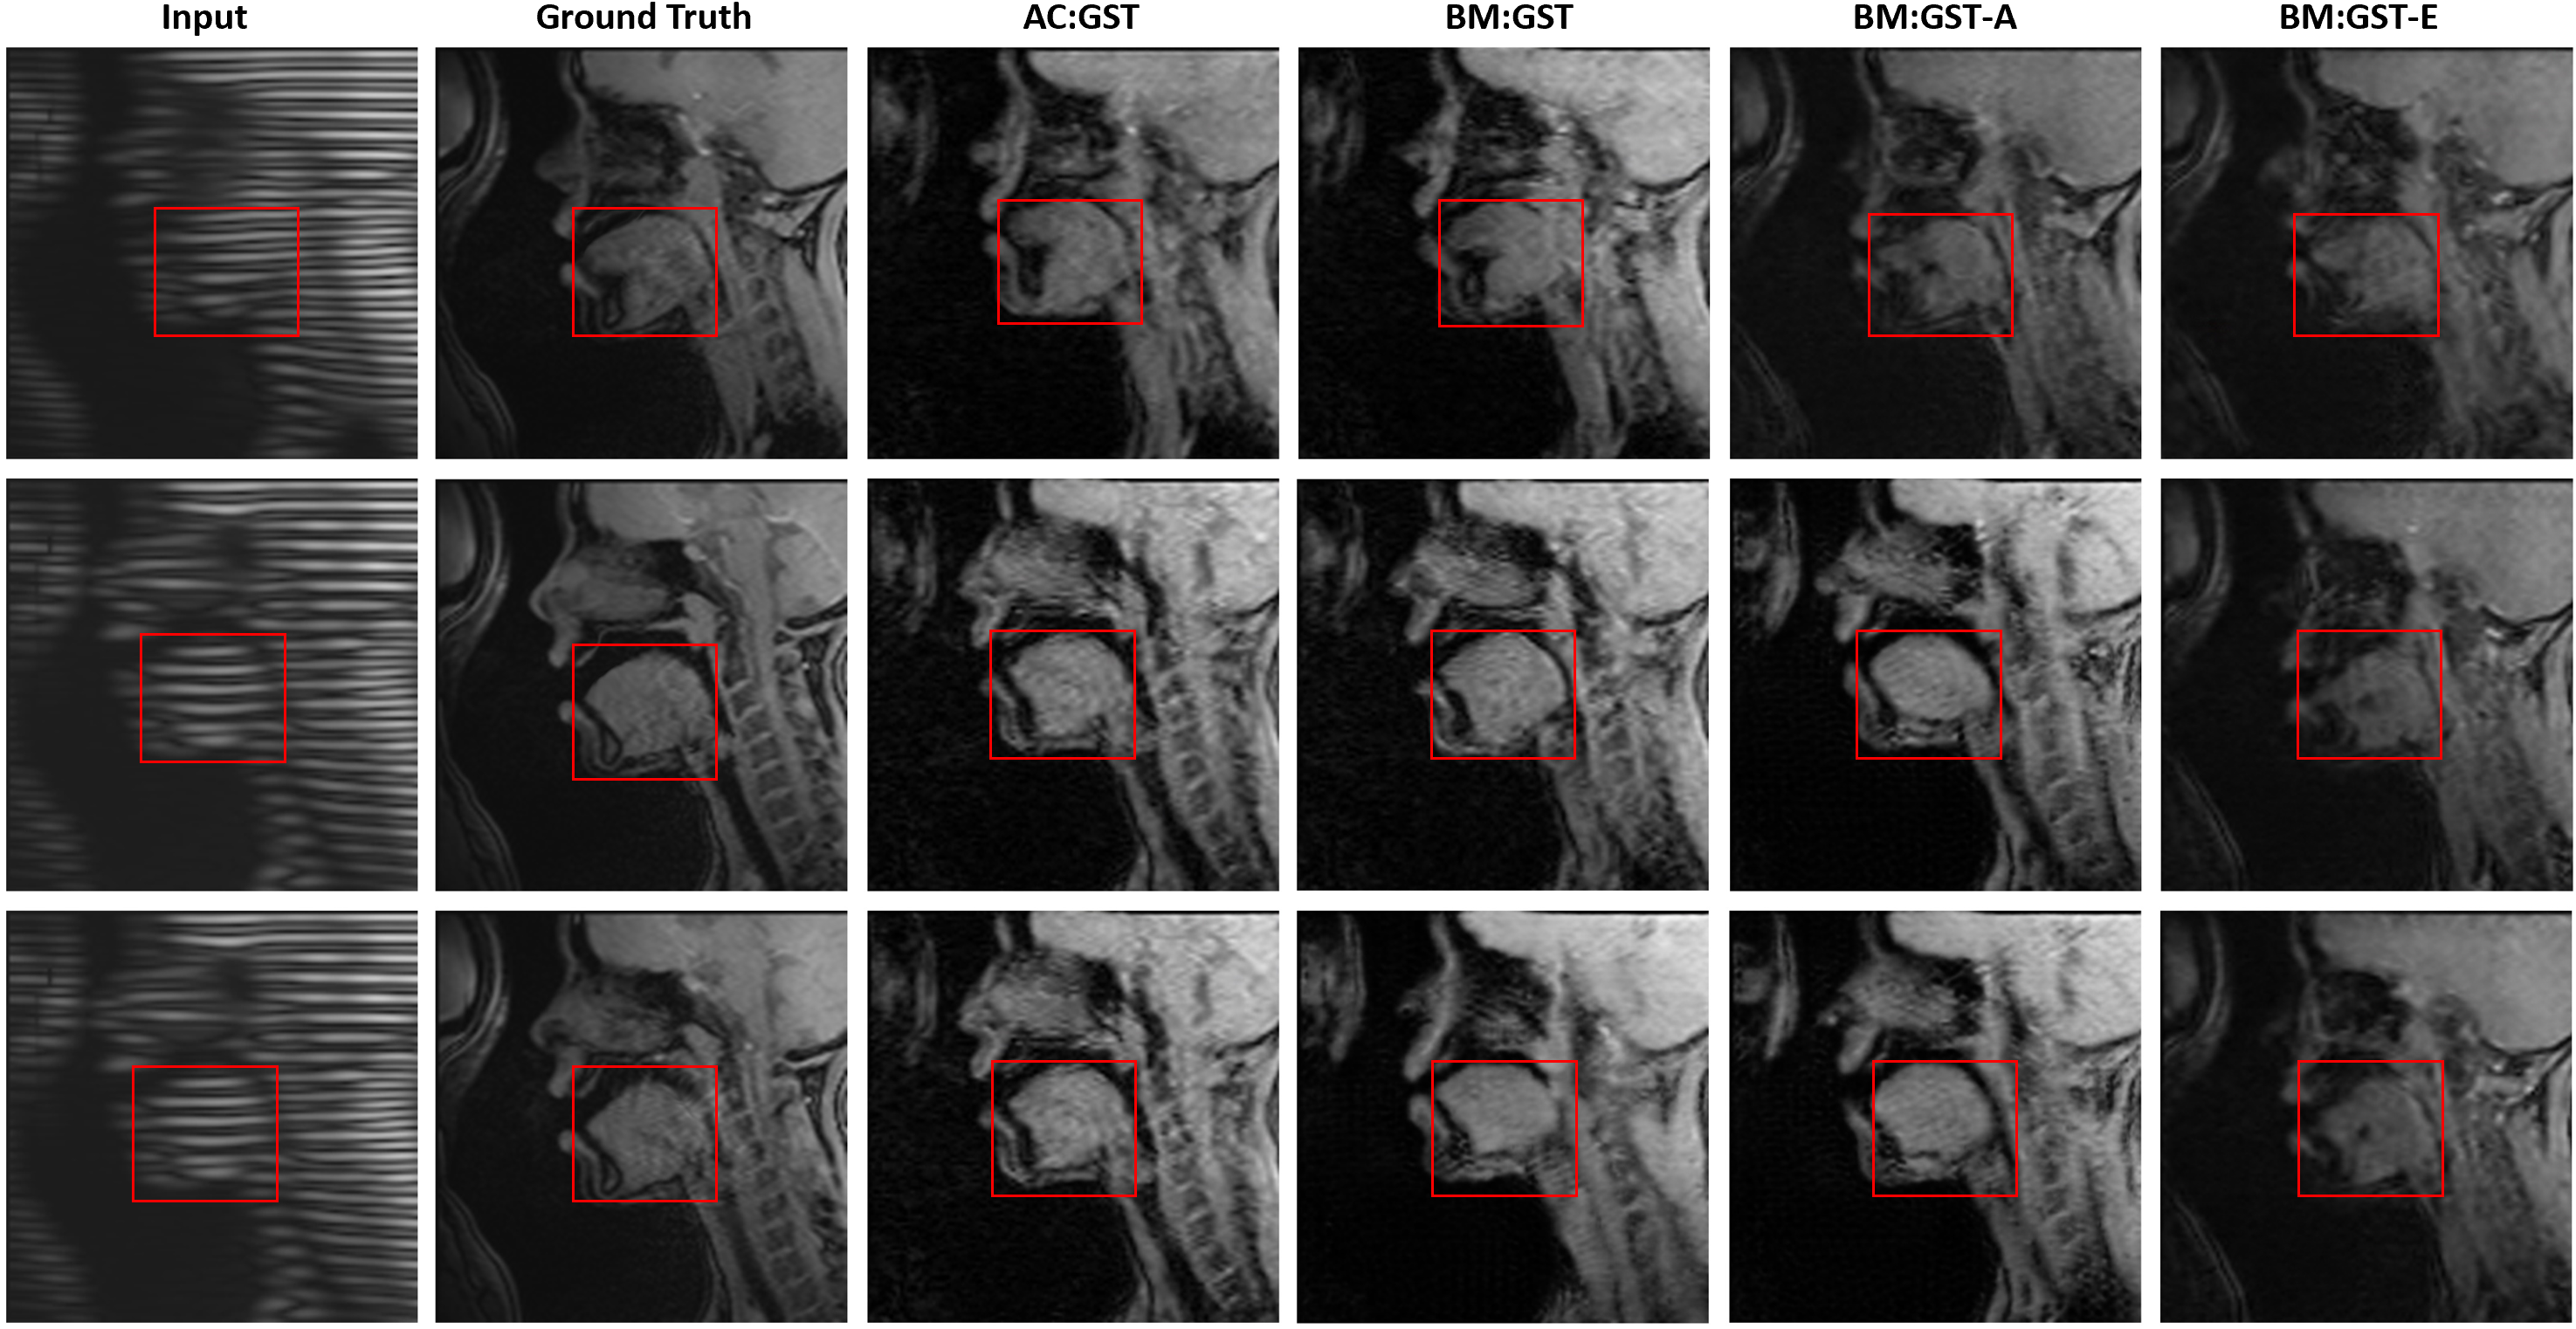

Refer to caption

Fig. 10: Ablation studies of our proposed AC:GST, BM:GST, BM:GST-A, and BM:GST-E for WUMinn-MGH cross-center T1-to-FA brain MR image translation. The red rectangle highlights the region with noticeable artifacts.

We provide qualitative comparisons against the adversarial UDA methods GAUDA [9] and ADDA [47] in Fig. 9. We carried out one-tailed paired t-tests for each of the L1, SSIM, PSNR, and IS metrics to compare improvements over BM:GST with AC:GST. The resulting p-values were 0.0140.0140.014, 0.0120.0120.012, 0.00760.00760.0076, and 6.09×1046.09superscript1046.09\times 10^{-4}, respectively, indicating statistical significance. When comparing AC:GST with JGLA, we obtained p-values of 0.00370.00370.0037, 0.00160.00160.0016, 2.65×1042.65superscript1042.65\times 10^{-4}, and 5.49×1055.49superscript1055.49\times 10^{-5} for the L1, SSIM, PSNR, and IS metrics, respectively, also indicating statistical significance. The ablation study results are shown in Fig. 10. In addition, the corresponding quantitative results are given in Table 3. In contrast to the tagged-to-cine MR translation task, our AC:GST framework outperformed the Pix2Pix baseline and adversarial UDA methods by a large margin. Of note, we empirically set weight β=0.75𝛽0.75\beta=0.75 and K=15𝐾15K=15, and provide the sensitivity analysis in Fig. 11. The results indicate that the performance of our model is relatively consistent for β[0.5,1.0]𝛽0.51.0\beta\in[0.5,1.0] and K15𝐾15K\geq 15.